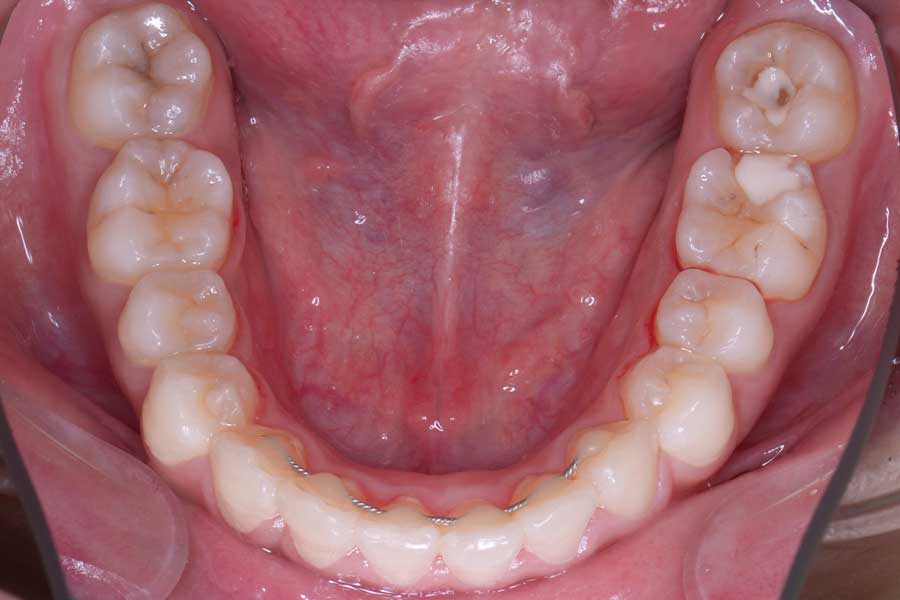

治療前

主訴 前歯の形と並びを良くしたい

治療内容 上下顎リンガル矯正(裏側矯正)